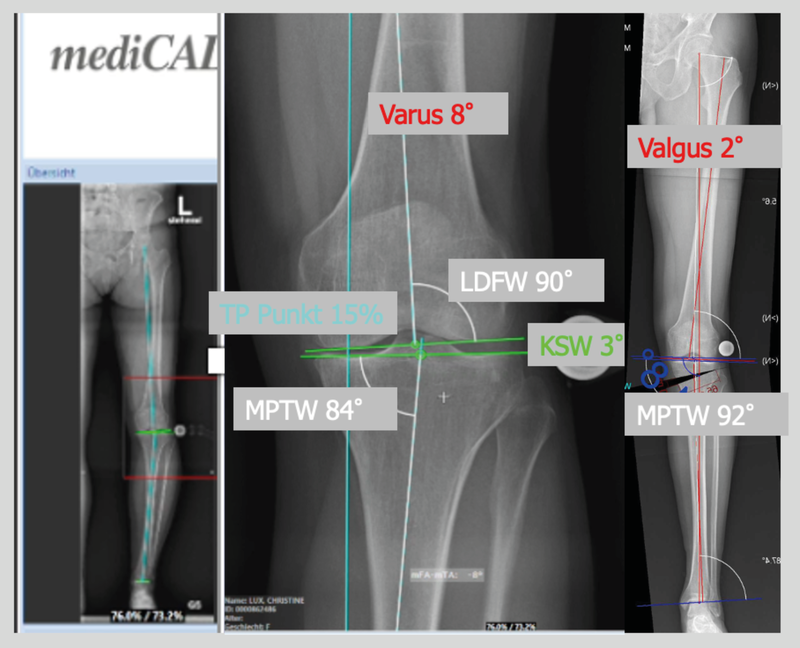

The deformity analysis of the full radiograph with the relevant measurements according to Dror-Paley (weight bearing line, mechanical axis, LDFA and MPTA) as well as the assessment of the joint line obliquity (JLO) and joint line convergence angle (JLCA) are of central importance. The planning for realignment osteotomy is standardized with an appropriate digital planning tool (e.g. mediCAD®). (Fig. 8)

An osteotomy will be revised with a total knee arthroplasty (TKA) after a mean service life of around 10−12 years. It can be technically very difficult to get a well-balanced TKA in a leg that has been overcorrected beyond the useful limits with any associated ligament mismatch or pathological jointline orientation [12] (Fig. 9).

For this reason, any overcorrection > 35% of the lateral tibia plateau (Fujisawa point) should be avoided and tighter correction limits for the joint line orientation (JLO) have emerged by now for the planning of axis correction. In practice this means that a correction of a high tibial osteotomy should not exceed the medial proximal tibial angle (MPTA) of 94°. In around 15% of cases a double level osteotomy is required to achieve this objective. A correctly indicated combination of cartilage repair and axis correction achieves good to very good results compared to the individual measures alone.